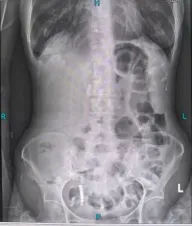

导管置入后,林奶奶的症状明显缓解,叶晋生通过进一步检查发现,林奶奶的肠梗阻并非单纯粘连所致,而是盆腔占位压迫肠道,考虑为子宫平滑肌肉瘤复发,且已侵犯直肠及膀胱,必须通过手术切除病灶才能从根源解决问题。叶晋生第一时间启动多学科会诊,麻醉科、ICU、消化科、肿瘤科等科室专家,共同评估病情及围手术期风险,